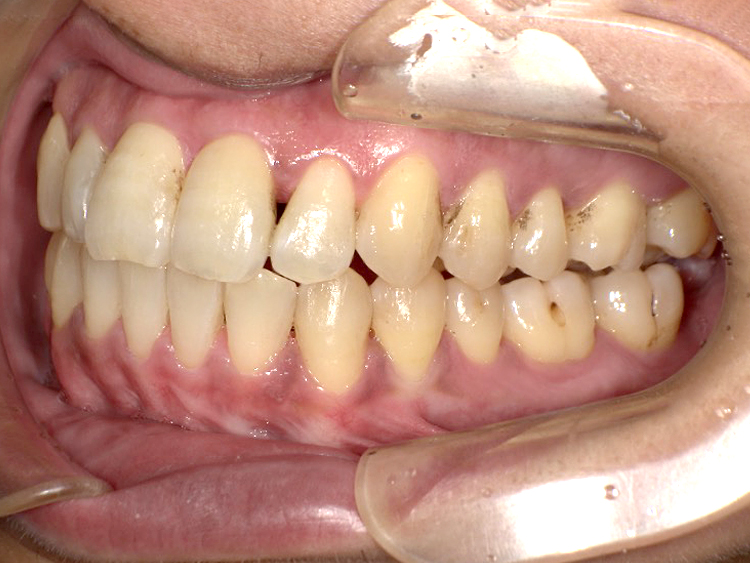

症例5

Before

After

| 主訴 | 上下3-3の並びが気になる |

|---|---|

| 年齢 | --- |

| 治療 期間 |

約1年 |

| 治療 内容 |

インビザライン5-5 |

| 治療費 | ¥517,000(税込)/調整料含む |

| 治療のリスク | 奥歯を動かさないので、前に出して並べていく。 歯と歯が移動するスペースを作るので、知覚過敏の症状がまれにでる。 歯を動かすことで、歯茎が下がるリスクある。 矯正終了後は、リテーナーを使用し、後戻りを防ぐ必要がある。 |